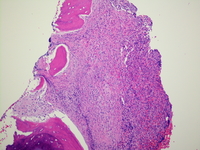

Category: Myeloid Neoplasms and acute leukemia (WHO 2016) > Mastocytosis > Systemic Mastocytosis (SM)

Moderately increased reticulin fibrosis in the area of the mast cell infiltrate (MF 2/3).